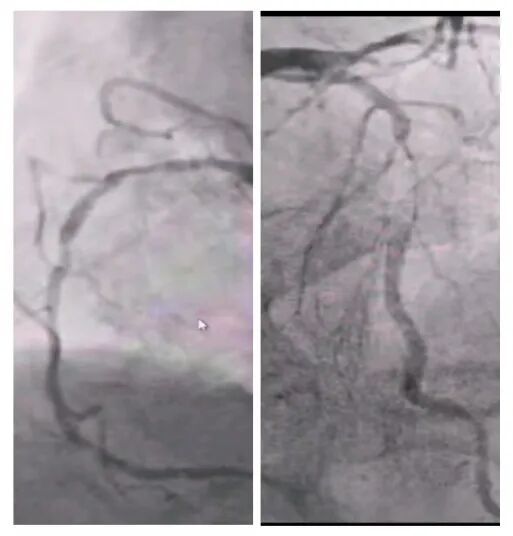

2025年深秋的一個清晨,82歲的馬奶奶(化名)因持續胸悶氣短被家人送至醫院心內科。心臟超聲檢查顯示,她的左心房內有一個直徑近5厘米的腫瘤,隨心跳規律擺動,如同一個隨時可能破裂的“不定時炸彈”。更危急的是,冠脈造影進一步揭示其冠狀動脈多支血管嚴重狹窄,左前降支狹窄達95%,回旋支中段完全閉塞,右冠狀動脈彌漫性病變—兩種致命性心臟疾病的疊加,讓這位高齡患者的生命岌岌可危。

術前冠脈造影